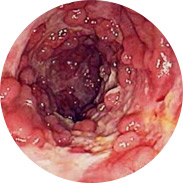

Quali sono i pericoli delleemorroidi negli uomini e nelle donne?

• Infiammazione della mucosa rettale e festering.

• Il sanguinamento può portare all'anemia

• L'aumento della temperatura corporea, con una grave infiammazione, può portare alla febbre.

• E il peggiore di tutti, il cancro al retto!